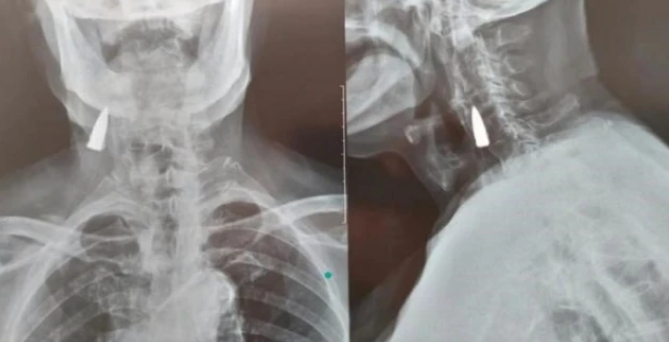

10月21日

山东临沂

一位95岁抗战老兵摔倒后

拍X光发现颈部

有一颗战争时期留下的子弹